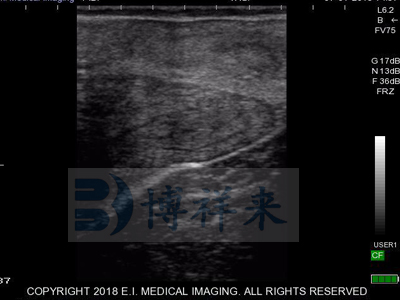

L7HD 高频线阵直肠探头(5-9MHZ可变) 高清分辨率

适用对象:牛马骆驼等大动物生殖检查、肌腱检查、新生犊牛肺部检查。